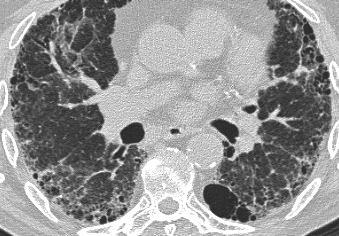

Hình bên trái là bệnh nhân bị tai nạn giao thông và trong vòng vài giờ đã phát triển ARDS.

Hình thái chiếm ưu thế là kính mờ (ground glass opacity).

Tại các vùng phụ thuộc trọng lực của phổi còn có thêm một số vùng đông đặc, tạo ra gradient từ trước ra sau.

Một đặc điểm quan trọng trong ARDS ngoài phổi là tính đối xứng của các bất thường.